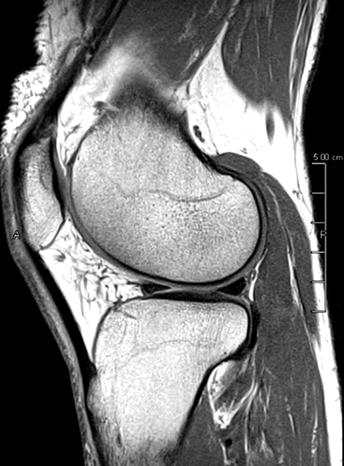

PD STIR - 1024 x 1024 matrix - 3mm slice thickness

Sag T2 - 0.5 x 0.5 min - 0:56 min Ax PD FatSat - 0.6 x 0.6 mm - 1:30 min Cor PD FatSat - 0.6 x 0.6 mm - 1:15 min Cor PD - 0.5 x 0.5 mm - 0:58 min © 2020 CANON MEDICAL SYSTEMS // MREU200040

Fast knee protocol with AiCE on Vantage Orian 1.5T